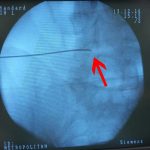

- Β. Τοποθέτηση βελόνας οδηγού (πλαγία λήψη)

- Γ. Έγχυση Disco-Gel εντός δίσκου (πλαγία λήψη)

- Δ. Ολοκλήρωση τεχνικής (Πλαγία λήψη)

Η επέμβαση πραγματοποιήθηκε εντός 20 λεπτών με τοπική αναισθησία, υπό συνεχή ακτινοσκοπικό έλεγχο. Έγινε έγχυση ενός κ.εκ. Disco-Gel εντός του μεσοσπονδύλιου δίσκου. Ο πάσχων επείτα μιας ώρας αναχώρησε από το νοσοκομείο.